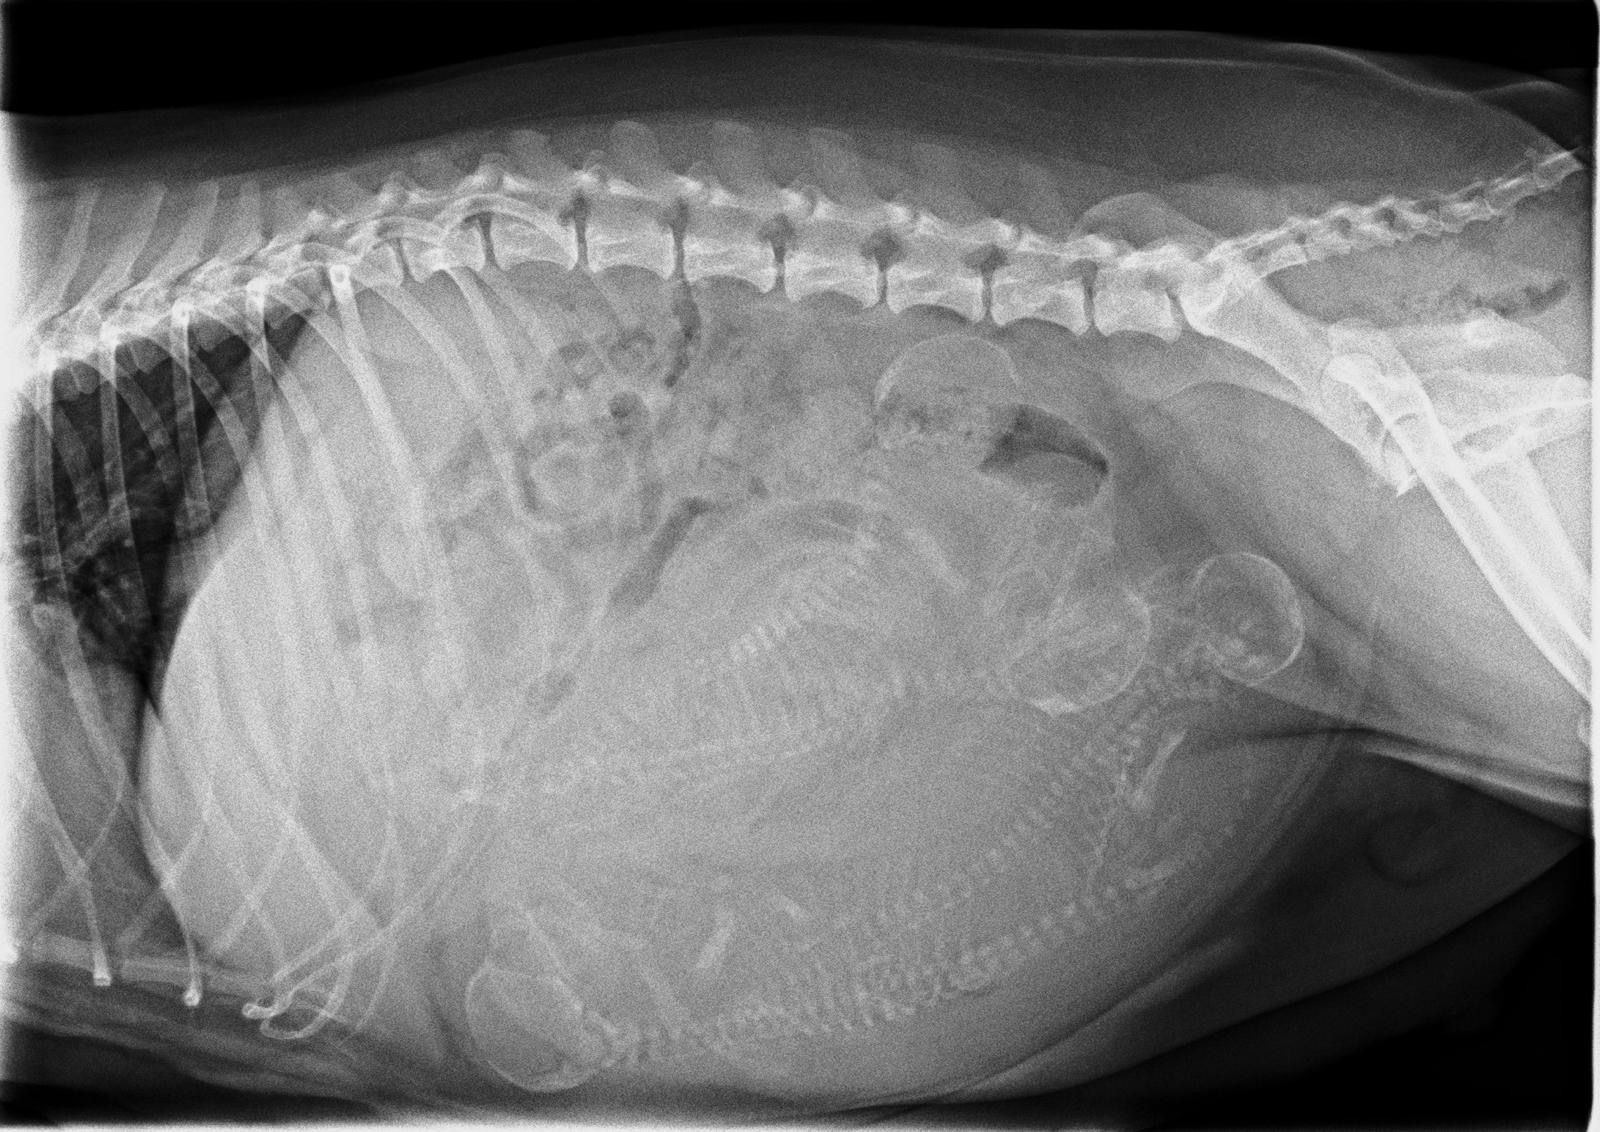

Rund 1 Woche vor dem berechneten Wurftermin war unsere Maite vom Nikolausberg bei unserer Tierärztin Dr. Marianne Fischer zum Röntgen. Wir wollten ja wissen, mit wie vielen "Fellnasen" wir rechnen können, auch um bei der Geburt etwas mehr Sicherheit zu haben, dass alles problemlos abläuft. Deutlich zu sehen sind 4 kleine Vierbeiner. Maite's Gewicht und Bauchumfang nehmen fortlaufend zu und sie ist etwas ruhiger geworden, kann, wie immer, nicht genügend zu fressen bekommen.